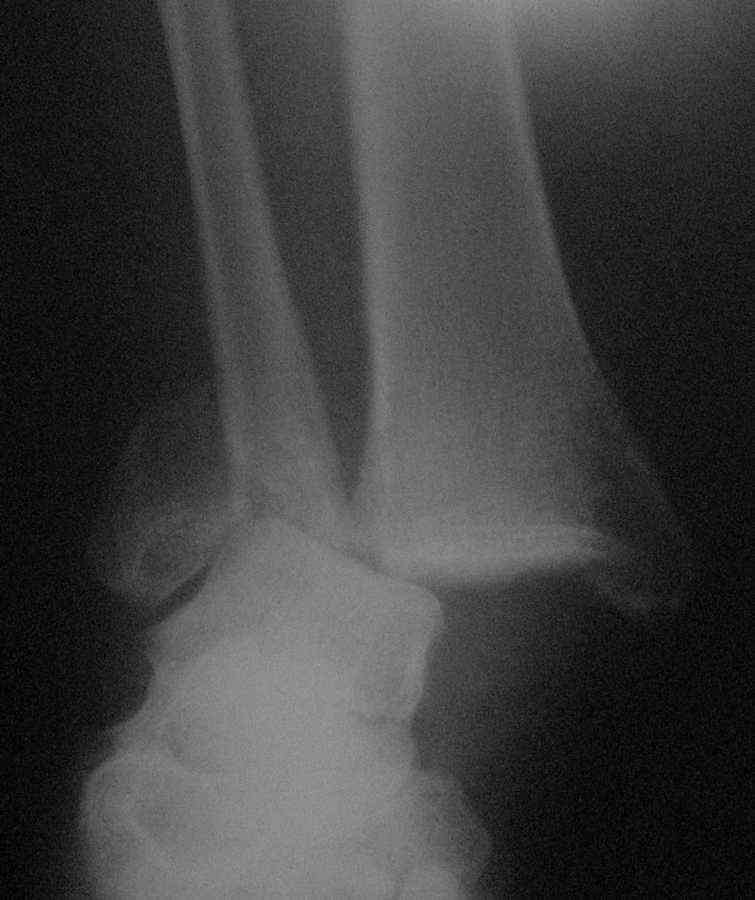

[Ortho] Застарелый перелом наружной лодыжки, разрыв дельтовидной связки, задне-наружный вывих стопы.

Сегодня, 19.11.09. поступила больная 37 лет с представленной рентгеновской картиной.

Анамнез травмы и заболевания следующий: 2.10.09 больная была направлена в приёмный покой с

Дз: закрытый перелом наружной лодыжки со смещением отломков. Больной при поступлении

выполнена закрытая репозиция, гипсовая иммобилизация U-образной лонгетой,

госпитализирована. На следующие сутки больная самовольно покинула отделение. Со слов

больной - лечилась дома самостоятельно, 15.11.09 вызвала хирурга на дом в связи с неприятным

запахом из под гипса, на дому хирург снял гипс, были отмечены нагноившиеся пролежни

циркулярно по задне-наружному краю стопы. Гипс был снят, проводилось местное лечение

хирургом на дому. Больная не пользовалась костылями, наступала на травмированную

конечность. После заживления ран направлена хирургом с Диагнозом: двухлодыжечный перелом

правой голени.

Дополнения к анамнезу: посттравматическая энцефалопатия, органическое

заболевание головного мозга, хронический гепатит "С". Ожирение. Предложены следующие

тактики лечения: 1. низведение стопы аппаратом. 2. артродезирование с использованием

аутотрансплантата, металлофиксация. 3 длительная гипсовая

иммобилизация. Либо одномоментное артродезирование с использованием

БИОС( ЭОПа нет и не будет, Гвоздь....б\у)Просим высказать ваше мнения

и предложения.